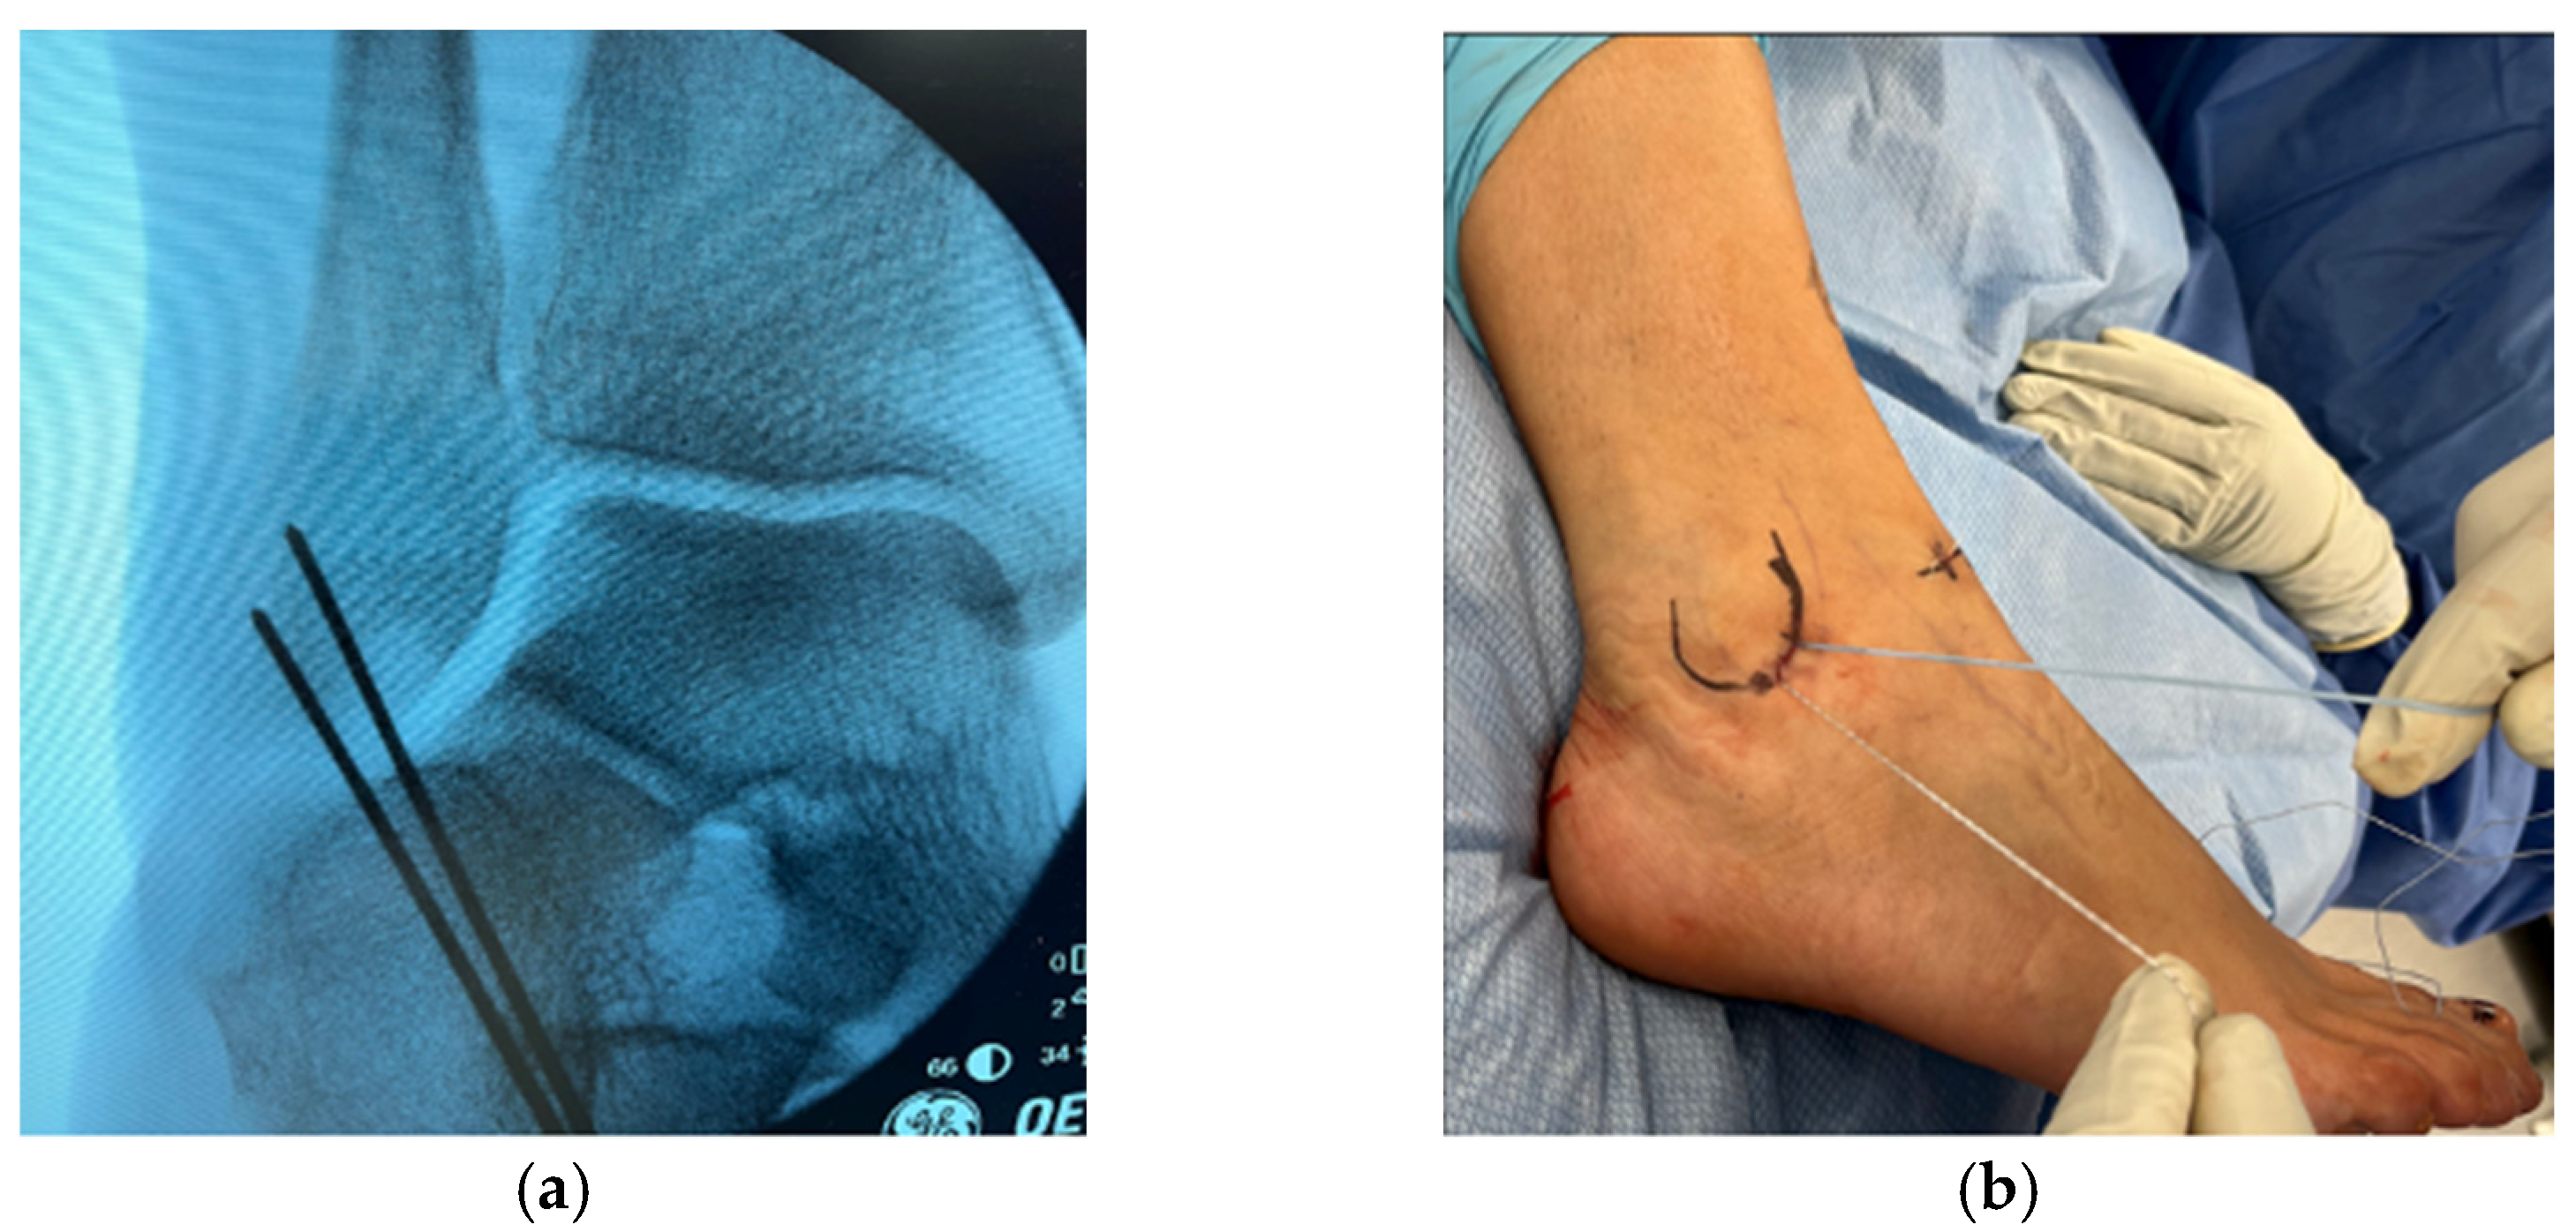

Two guidewires were advanced under fluoroscopic guidance at the footprint of the ATFL. The wires were spaced 1 cm apart. The skin was incised over the wires, and the latter were then overdrilled, followed by insertion of a 3 mm BioComposite suture anchor (Arthrobrostrom, Arthex, Naples, FL, USA) (Figure 2).

Figure 2. (a) Positioning of k-wires under fluoroscopic guidance. (b) Suture anchors at the midpoint of the ATFL and CFL.